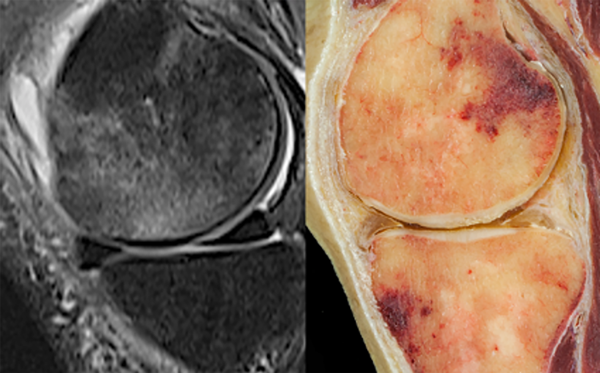

El cartílago articular y el hueso subcondral actúan como una unidad funcional, la unidad osteocondral (UOC) (fig. 1), que junto con la membrana sinovial se encargan de mantener la homeostasis del órgano articular. Numerosos esfuerzos de investigación se han centrado en el daño del cartílago articular, mientras que relativamente pocos se centran en la patología ósea subcondral.12-14 Las LMO representan una alteración de la intensidad de la señal de la médula ósea, con alta señal en secuencias sensibles a fluidos (densidad T2/protones con supresión de grasa y recuperación de inversión tau corta (STIR) (fig. 2A) con o sin señal T1WI baja por resonancia magnética (RM).

Figura 1: Sección sagital del cóndilo femoral lateral que muestra una lesión que compromete la unidad osteocondral.

Figura 2: A) Resonancia magnética de rodilla (vista sagital) con una lesión del hueso subcondral en el cóndilo femoral. B) Vista sagital de una disección anatómica de rodilla con hemorragia en el hueso subcondral en fémur y tibia.